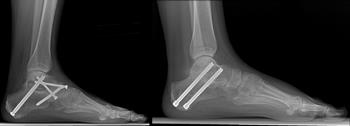

Midfoot (Middle of the Foot)

Fusion is the most reliable surgical method to treat RA of the midfoot joints. If the shape of the foot is not normal, surgery is designed to help restore the arch and minimize the prominences (bumps) on the foot.

Although the foot cannot be returned to a normal shape, the goals are to reduce pain in the foot and improve the potential for the patient to wear more normal shoes.